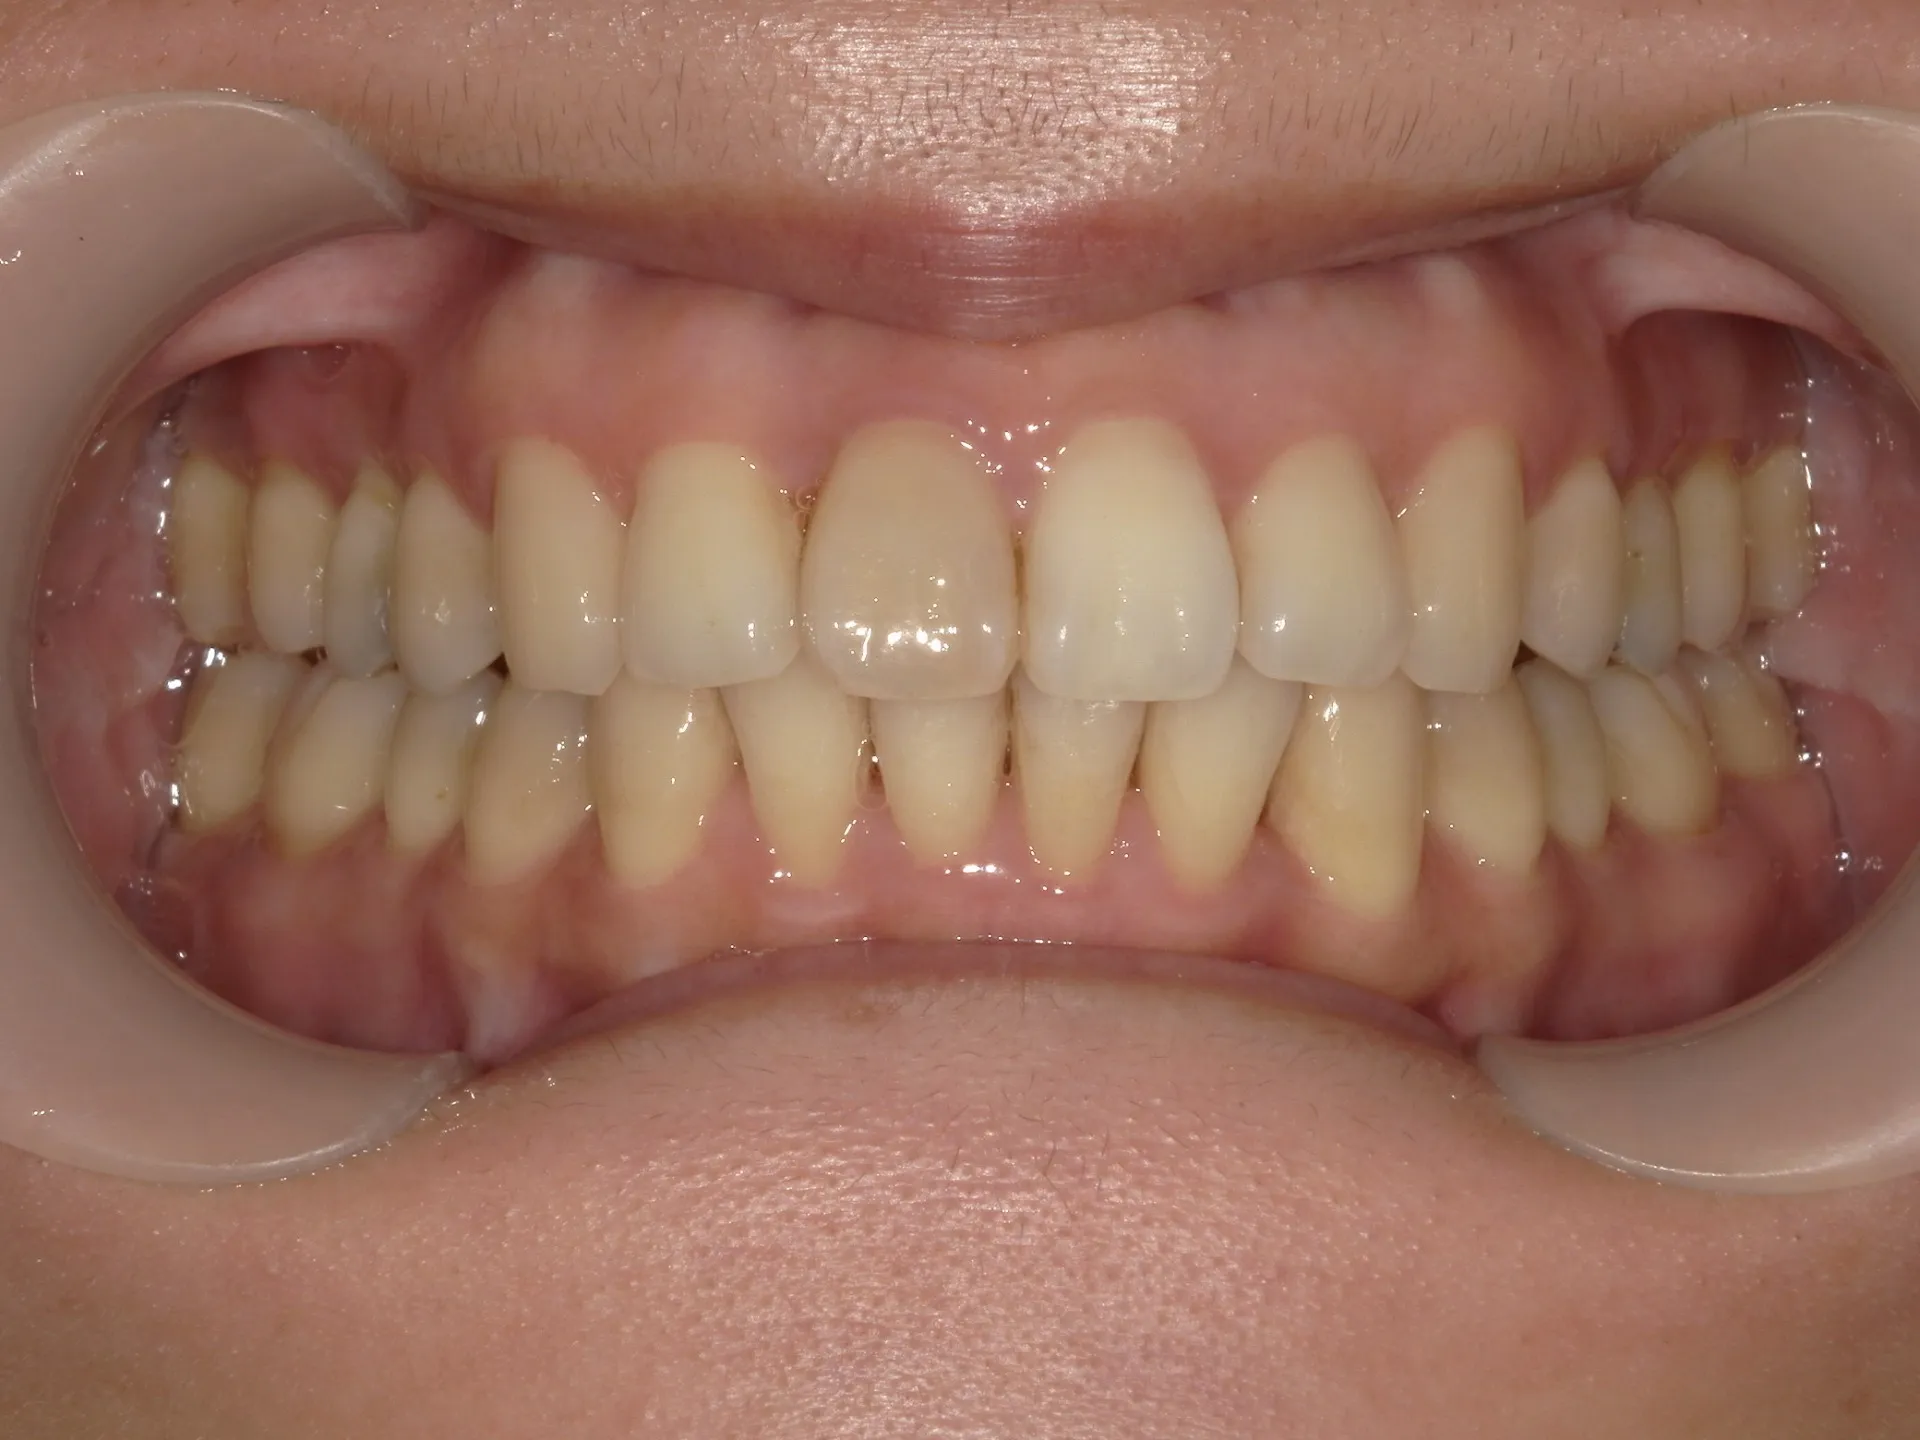

今回はねじれてしまった前歯の矯正治療をインビザラインというマウスピース矯正で治療した症例をご紹介いたします。